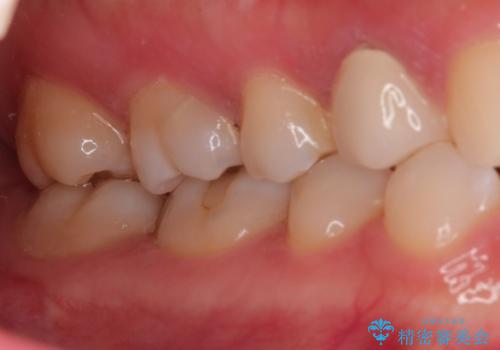

【VPT(歯髄温存療法)とセラミックインレー】深い虫歯でも神経を残したい

- 虫歯が大きく神経まで達していたので、VPT(歯髄温存療法)を行って細菌感染した部分の神経のみ取り除き、保存可能な神経は保存し被せ物はセラミックインレーで治療を行いました。